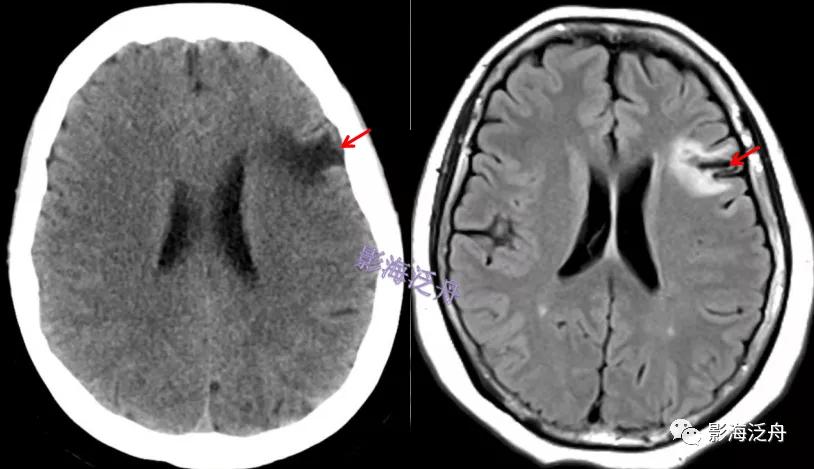

如何根据头颅ct预判超早期脑梗死?

头颅ct如何预判超早期脑梗死